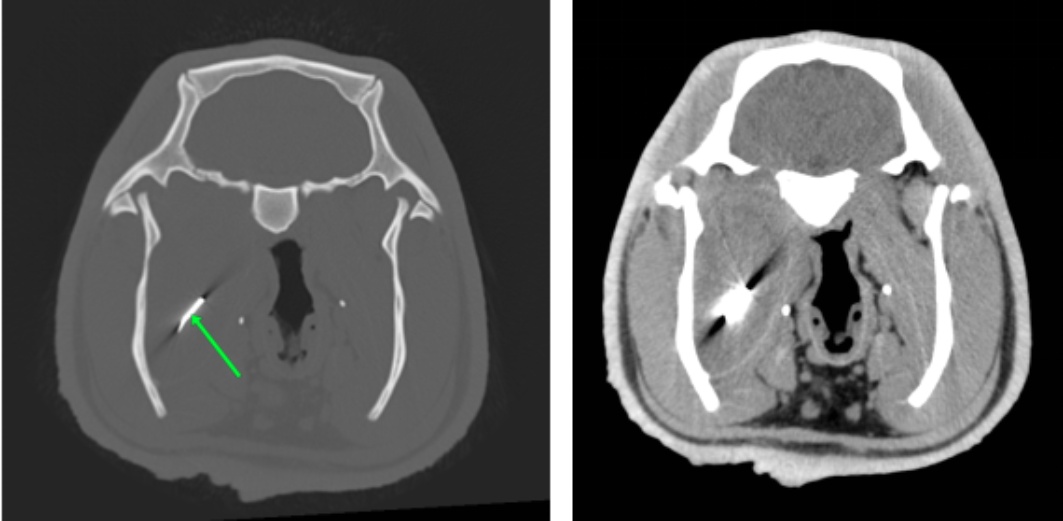

使用万东医疗的OpenCT机,将患病水豚以背卧位及侧卧位保定进行头部平扫和三维成像,影像结果见图1图2

图1(A)可知,其右侧喉咽部会厌水平处有一细棒状金属密度异物影,长度约1.8 cm,周围软组织密度降低,软组织内有多个小气泡影。由图1(B)可知其双侧颞下颌关节未有明显脱位。由图1(C)可知,其右侧鼓室重力侧有层状中等密度影,左侧鼓室内充满气体影,外耳道通畅,耳道壁有点状钙化灶。各牙齿密度正常,齿根处无明显骨质溶解,未有齿根过长,双侧切齿对合良好。脑中线居中,脑实质无明显异常密度影。鼻中隔居中,筛骨完整、对称,鼻腔内无明显渗出影。

Figure 1. CT image of diseased capybara

1. 患病水豚CT影像

基于CT影像结果,计划进行异物取出手术。术前通过对患病水豚的DR检查重新定位异物位置,同时评估其胸腹部情况。影像学结果显示:金属异物位于右侧下颌骨后缘内侧,位置较深;胸腔未见明显异常改变;腹腔可见不同程度肠道积气。综合评估后确认具备手术指征。术前为其建立静脉通路并置入留置针,以2 mg/kg剂量的舒泰50进行初步镇静,诱导期约15 min。随后实施气管插管,采用异氟烷吸入麻醉维持,同时以200 mL/h的速度进行静脉补液。